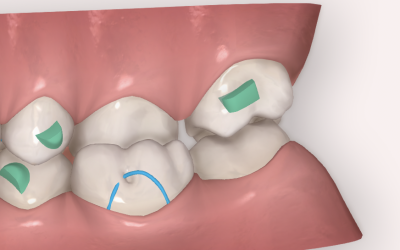

Extracción de incisivo inferior en adultos: qué diente extraer y cómo cerrar el espacio con alineadores

La extracción de un incisivo mandibular sigue siendo una herramienta válida en casos seleccionados que presentan apiñamiento anterior localizado o discrepancia Bolton anterior significativa. Con alineadores, el principal desafío es lograr un cierre de espacio...